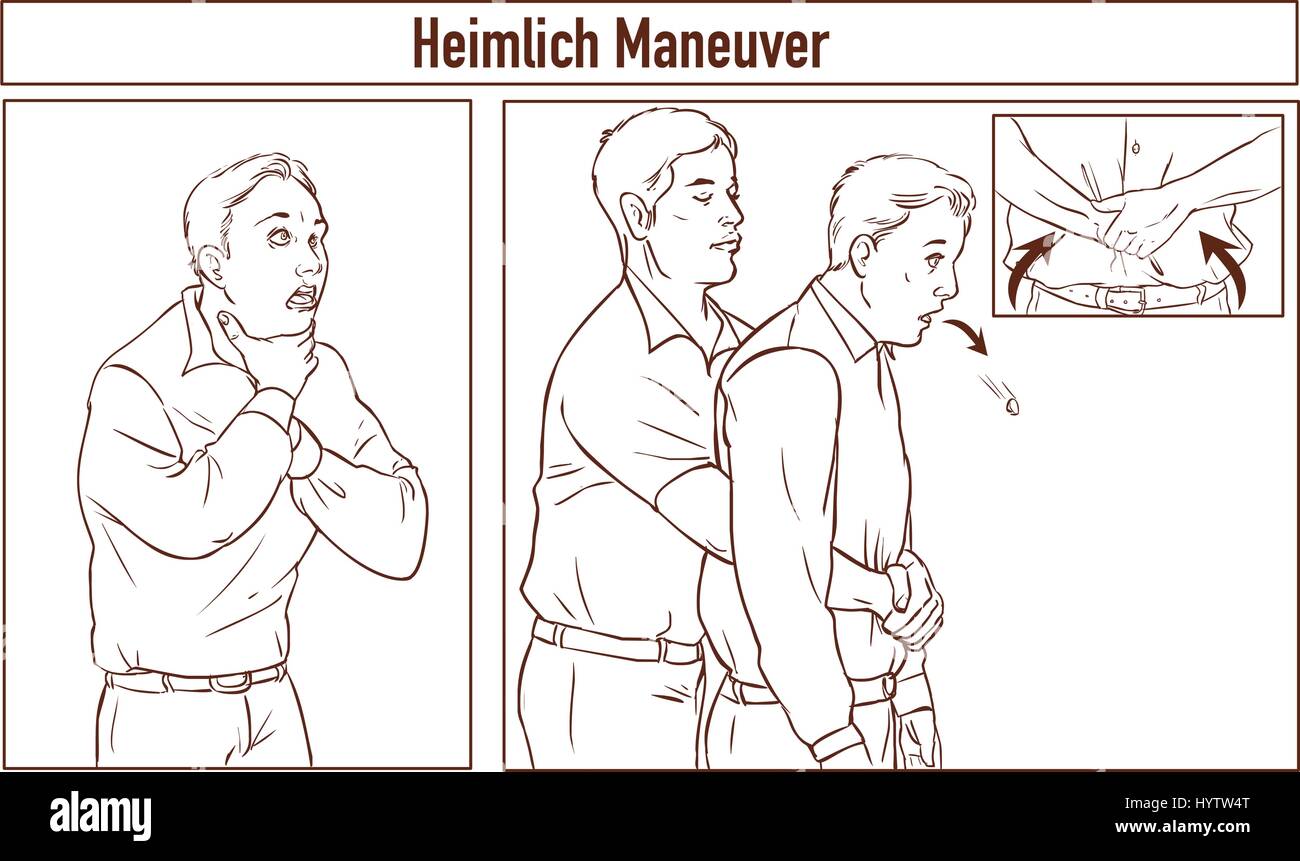

Clip Art of One man stands behind the conscious victim with his hands in the proper position on the victim's abdomen to perform the Heimlich maneuver Stock Vectorhttps://www.alamy.com/image-license-details/?v=1https://www.alamy.com/stock-photo-clip-art-of-one-man-stands-behind-the-conscious-victim-with-his-hands-137614872.html

Clip Art of One man stands behind the conscious victim with his hands in the proper position on the victim's abdomen to perform the Heimlich maneuver Stock Vectorhttps://www.alamy.com/image-license-details/?v=1https://www.alamy.com/stock-photo-clip-art-of-one-man-stands-behind-the-conscious-victim-with-his-hands-137614872.htmlRFHYTW4T–Clip Art of One man stands behind the conscious victim with his hands in the proper position on the victim's abdomen to perform the Heimlich maneuver